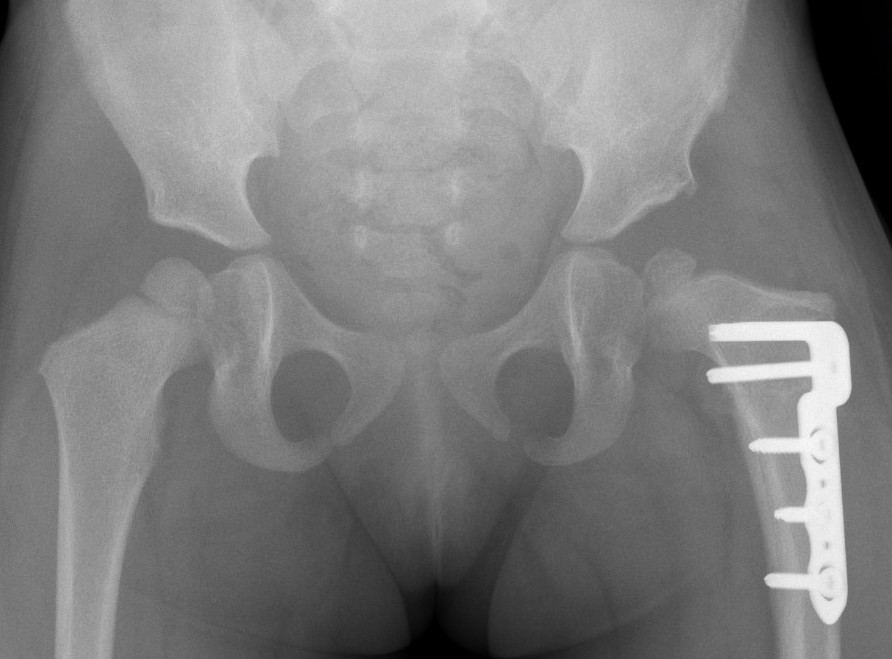

Xray

Dislocated hips in the setting of DDH with ncreased acetabular index

Femoral Varus Derotation Osteotomy (VDRO)

Indication

Tight reduction risking AVN

Unstable reduction with increased femoral anteversion

Increased femoral neck angle